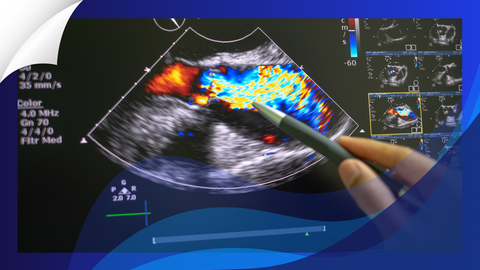

In a comprehensive multimodality imaging study, Ozbay and colleagues provide compelling evidence that the left atrium itself is intrinsically diseased in ATTR-CM—and that this primary atrial cardiopathy independently contributes to thrombotic risk.

In a propensity-matched cohort of 104 patients with ATTR-CM and 104 patients with non-amyloid left ventricular hypertrophy (LVH), the atrial phenotype diverged in clinically meaningful ways. Left atrial reservoir strain (LASr) was markedly reduced in ATTR-CM (approximately 10% vs 17% in LVH), while left atrial stiffness was more than doubled (median ~2.1 vs 0.9 1/%). These abnormalities were present despite smaller or only mildly enlarged left atrial volumes in ATTR-CM.

Instead, mechanical parameters carried prognostic weight. An LASr threshold of 9% or lower was associated with a 7.8-fold increased risk of thrombotic events after adjustment for atrial fibrillation. An atrial stiffness value of 1.7 or greater conferred roughly a fourfold increased risk. Left atrial volume index did not predict events, reinforcing that deformation and stiffness—not size—capture the clinically relevant substrate.

For clinicians, the implications are pragmatic. Reliance on CHA₂DS₂-VASc scoring alone is insufficient in cardiac amyloidosis. Incorporating left atrial strain and stiffness—obtainable through speckle-tracking echocardiography—may improve risk stratification. While prospective randomized data are needed before recommending anticoagulation solely on the basis of impaired atrial mechanics, this study provides a strong physiologic rationale for rethinking how thromboembolic prevention is approached in ATTR-CM.